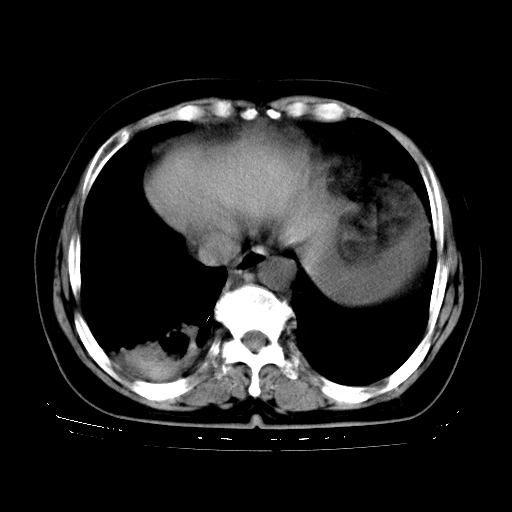

以下是引用zhangzhongshou在2008-3-22 12:52:00的发言:[br]1、右侧液气胸。[br]2、腹水。建议进一步检查。

以下是引用鲁巨ct在2008-3-22 14:10:00的发言:[br]1、右侧液气胸,右中下叶节段性不张。[br]2、腹水,建议上腹部ct检查

以下是引用zjzjr在2008-3-22 17:19:00的发言:[br]1、右侧液气胸,右下叶节段性不张。[br]2、腹水,建议上腹部ct检查